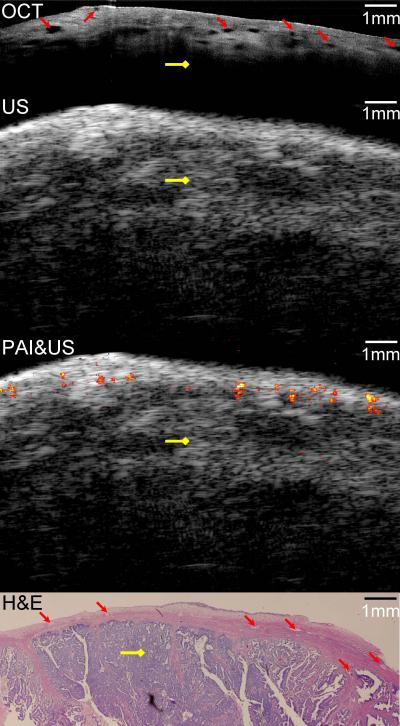

For their diagnostic device, the researchers combined the contrast provided by photoacoustic imaging, the high-resolution subsurface imaging provided by optical coherence tomography, and the deeper tissue imaging provided by pulse-echo ultrasound. They tested their device, described by the team in the September issue of the Optical Society's (OSA) open-access journal Biomedical Optics Express, by imaging both pig and human ovarian tissue, and correctly identified malignant tumors that were later confirmed by staining the tissue and examining it under a microscope. These initial tests were performed on tissue that had been surgically removed, but the diameter of the device – at only 5 mm – is small enough that it could potentially be inserted through a small slit to image tissue in live patients.